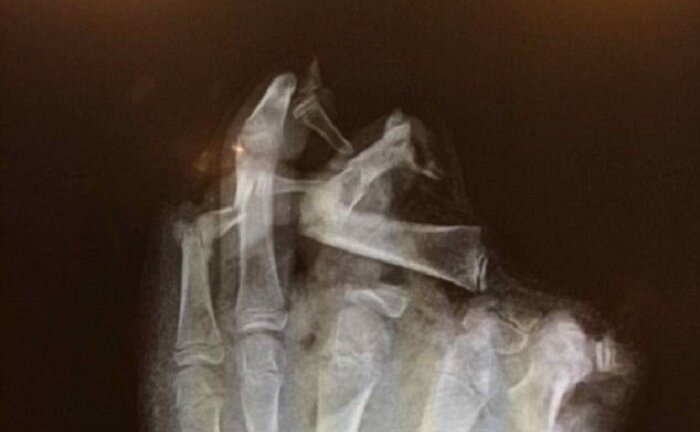

Bàn tay của một thanh niên đã bị mất ba ngón tay (gồm ngón cái, ngón trỏ và ngón giữa) sau khi chơi pháo trong đêm lửa trại.